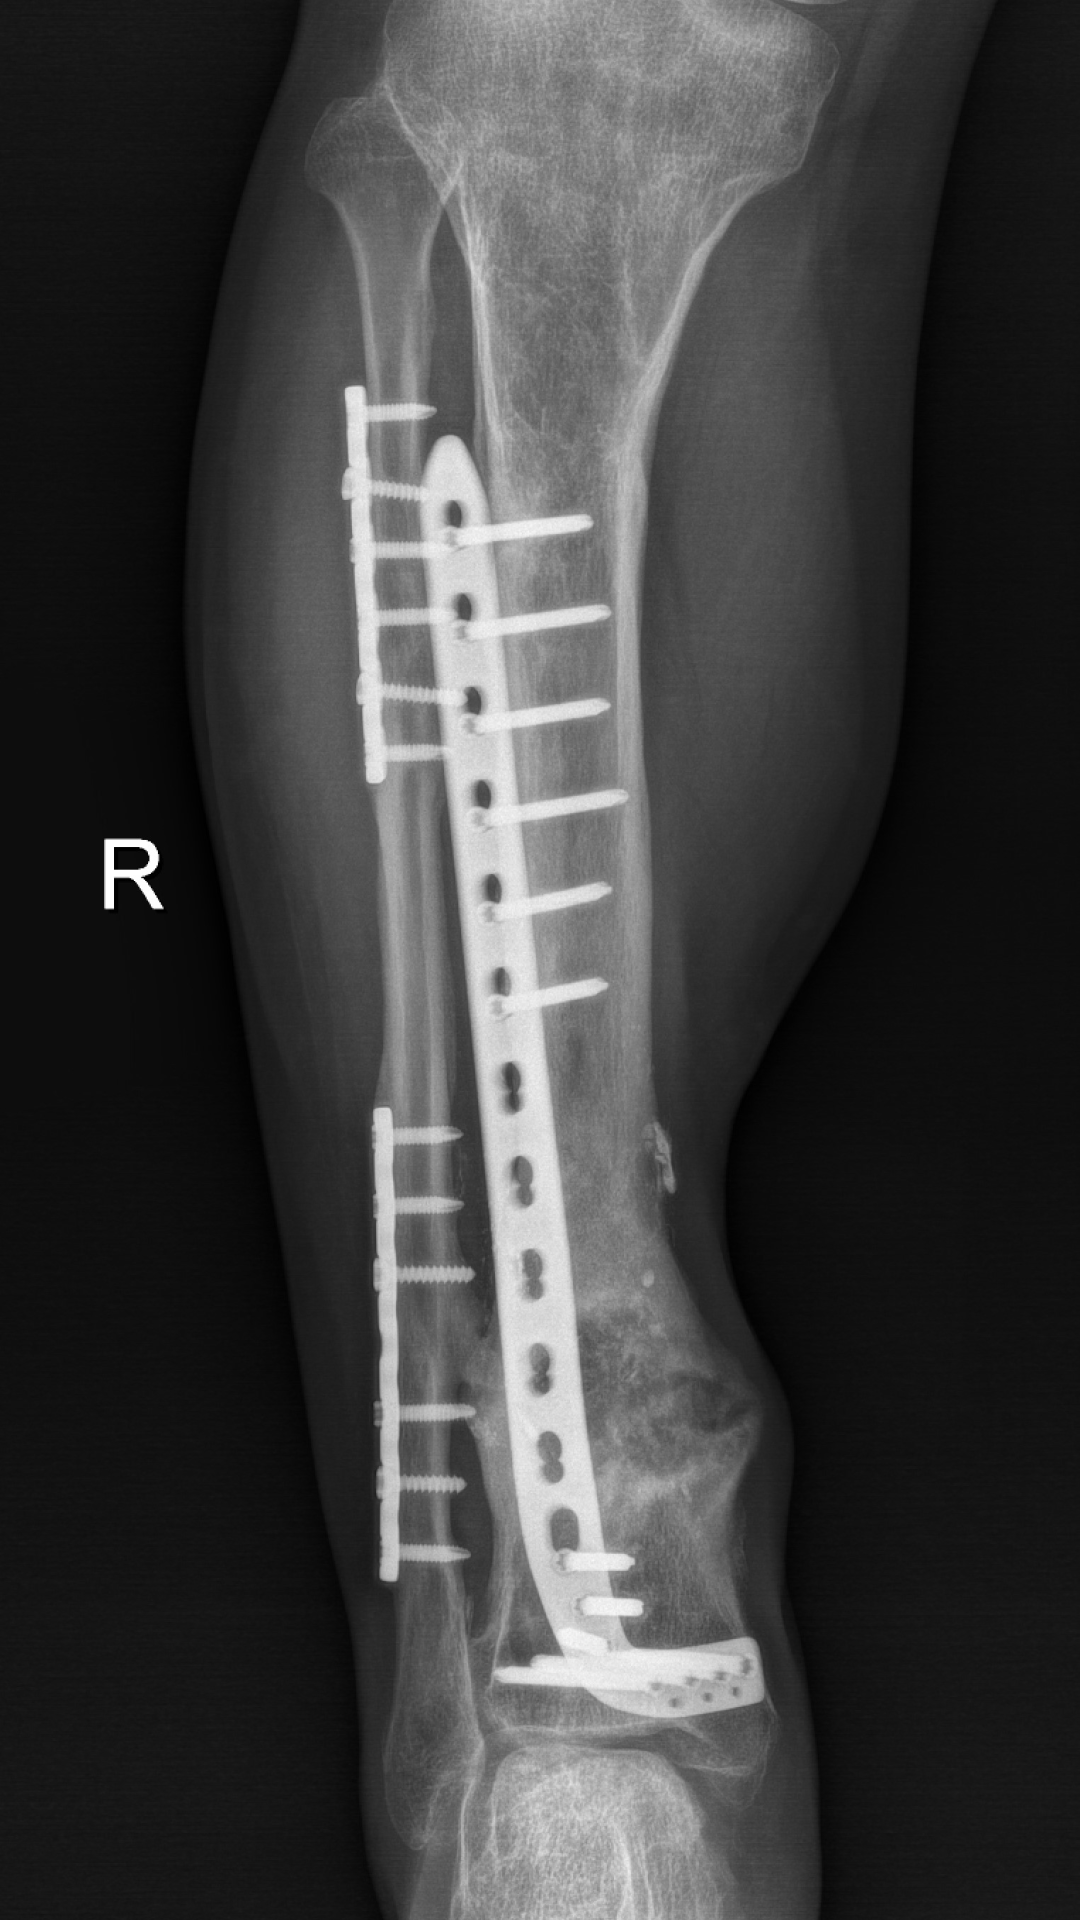

经过反复评估及推敲,徐杨主任医师决定分三步进行:首先分次清创,在保住残留血供及神经同时,彻底清创;利用长管状骨节段性缺损诱导膜再生技术(masquelet技术)修复骨缺损,最后通过肌腱转位替代、踝关节松解,恢复功能。这其中每一步都不容有失,困难重重,极具挑战。在医患通力配合下,多次按既定方案为小罗成功施行手术,小罗保住了右腿,经过近一年的正常行走生活,近日返院进行最后的钢板拆除手术。

4、内固定去除

多年来,我院骨一科徐杨主任医师团队致力于骨与软组织缺损修复研究,行成了独特的技术手段并制定了行之有效的诊疗规范,目前已成功救治多例大范围骨与软组织缺损病例,大大提高了保肢成功率。